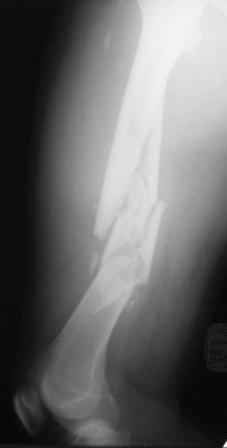

Хотелось узнать Ваше мнение по тактике лечения многооскольчатого перелома бедра Пациент 26 лет, травма в результате ДТП. Находится на системе скелетного вытяжения. Соматически уже компенсирован. Планируется выполнить остеосинтез бедренной LCP пластиной на тракционном столе, при этом не хотим обнажать зону многооскольчатого перелома. Буду благодарен за критические замечания по предложенной тактике и другие светлые мысли!

Выбор на пластине основан на том, что проксимальный отломок не цельный, по рентгенограмме видно, что в нём практически до малого вертела имеется осколок. Поэтому у меня опасения, что фиксация внутрикостного стержня в проксимальном отломке не будет достаточно стабильной.

Если суставные концы целы (что по приведенному

снимку не очевидно, но будем надеяться, что это так), то сразу подумалось про закрытый интрамедуллярный остеосинтез.